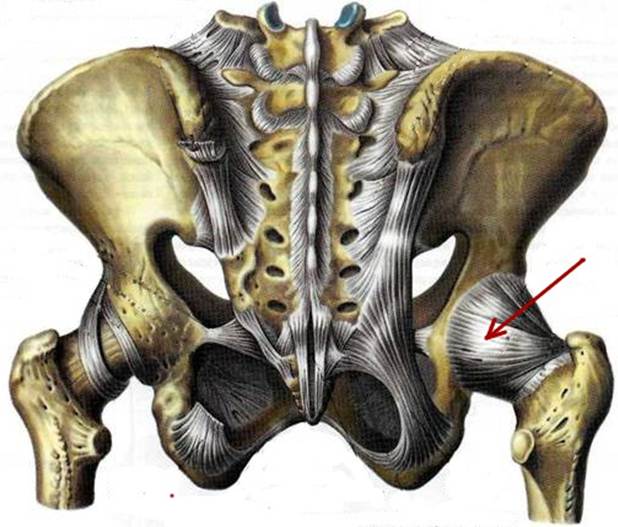

S: На рисунке обозначен art. Coxae (латинский язык).

S: Стрелка указывает на zona orbicularis

S: Стрелка указывает на lig. Ischiofemorale

S: Стрелки указывают на lig. iliofemorale

S: Стрелка указывает на lig. pubofemorale